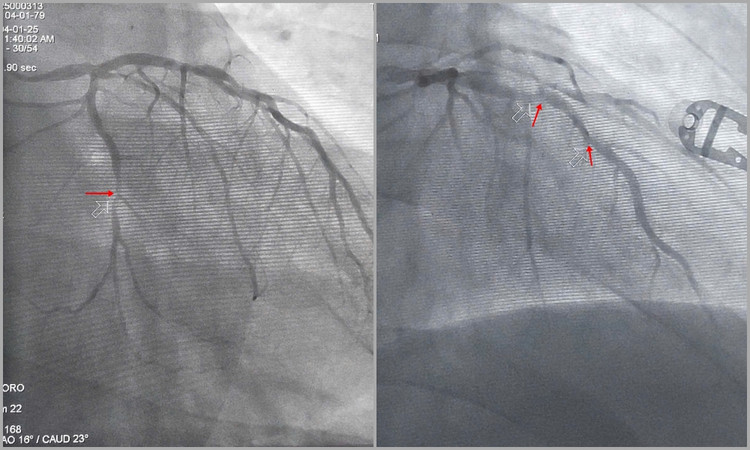

Kết quả chụp mạch cho thấy 3 thân động mạch vành tổn thương nặng, huyết khối làm tắc cấp tính hoàn toàn động mạch vành phải, động mạch mũ và động mạch liên thất trước hẹp nặng.

| Hình ảnh động mạch mũ (trái) và động mạch liên thất trước (phải) hẹp nặng. |

| Hình ảnh động mạch mũ (trái) và động mạch liên thất trước (phải) hẹp nặng - Ảnh BSCC |